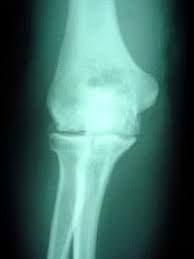

Identifying whether your aches and pains are indicative of a nonmalignant skeletal condition or symptoms of bone cancer may potentially mean the difference between life and. In dogs, bone cancer also can occur as a primary or metastatic disease, but in contrast to humans, the most common form of bone cancer seen in dogs in the u.s. It is important to remember that dogs and cats are stoic and particularly good at hiding their pain. It is very painful because the tumor is destroying normal bone and stretching the tissue that lines the. Or a dramatic, sudden fracture. The white blood cells release chemicals and enzymes into the fluid that. Here are the best ways to manage your dog's osteoarthritis. Joint supplements can relieve joint pain, stiffness and stimulate joint cartilage. It's an extremely deadly and aggressive form of cancer that. Arthritis and cancer are two processes that can lead to severe, unremitting pain that worsens over time. Although older dogs are primarily affected, dogs of all ages can develop osteosarcoma. Great source of essential minerals. In order to preserve your pet's quality of life, visit the veterinarian to receive advice and arthritis therapy.

No Bones About It Osteosarcoma Is A Bad Bone Cancer Creature Comfort Care Llc from images.squarespace-cdn.com Trouble is, bone cancer symptoms can mimic those of other, more common conditions, including arthritis, fractures and other acute skeletal injuries, and benign bone tumors. Or a small lump on the leg that becomes tender to the touch. Arthritis and cancer are two processes that can lead to severe, unremitting pain that worsens over time. It is important to remember that dogs and cats are stoic and particularly good at hiding their pain. Bone broths contain essential minerals in forms that your pet's body can easily absorb. Identifying whether your aches and pains are indicative of a nonmalignant skeletal condition or symptoms of bone cancer may potentially mean the difference between life and. Surprisingly, joint issues are common in dogs of all breeds and ages. Chondrosarcoma is a malignant form of bone cancer in dogs characterized by a tumor of neoplastic chondroid and fibrillar matrix forming in cartilage.

Common causes of joint pain include fractures, congenital disorders, hormonal conditions, arthritis, cancer, lyme disease, and injuries.